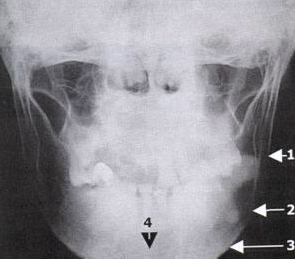

Caldwell View

Evaluation The Upper And Middle Thirds Of The Face